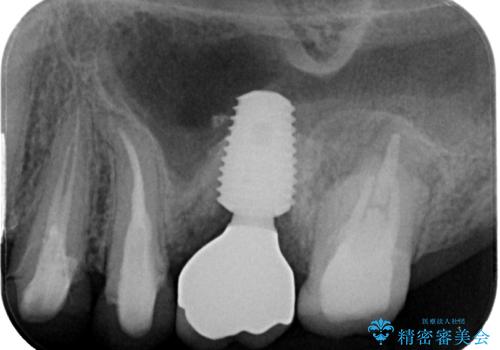

垂直方向への炎症が大きく、抜歯即時埋入はできたものの、即時荷重(インプラント埋入時の仮歯の装着)を可能とする安定値は得られませんでした。

それにもかかわらず、僅か4ヶ月で治療を終えることができ、以前の上顎洞底の挙上を行っていた頃よりも半年以上短縮することができました。